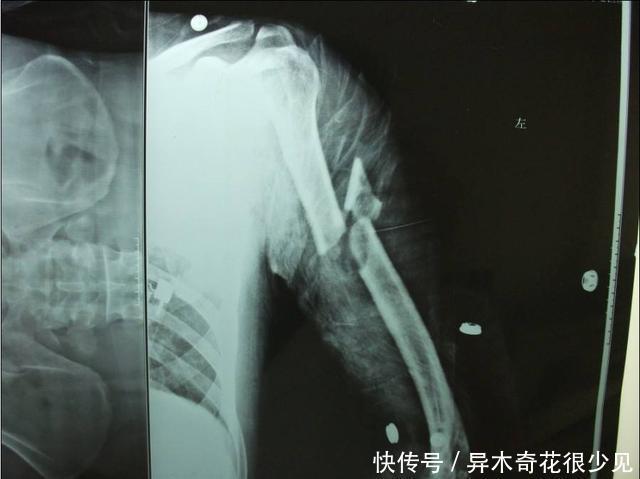

文章图片

骨肿瘤造成的肉眼可见的肿块

很多患者都是因为身上长了一个大肿块才来医院就诊的。这种肿块一般会很快很快的迅速的长大。这种迅速长大的肿块,一般来说都是恶性肿瘤。还有恶性肿瘤有这样一个特点,他们局部的血管一般都暴露得很明显,在人体表面就可以看到肿瘤的血管怒张着。这表明肿瘤内部的血运是十分丰富的,这种情况多数都是恶性的。

而相对的,良性肿瘤一般摸上去是比较硬的,而且按上去不会疼痛的肿块,很多时候,皮肤的温度跟其他部位的温度是一样的,不会有显著发热的表现。而且一般不会在上面看到有血管的走形。这种肿块的生长特点是长得比较缓慢。一般来说都是在偶然间发现的。很多人甚至长了很久的良性肿块都不会发现。